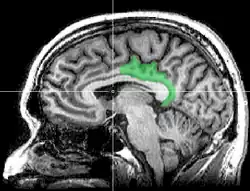

Cortex cingulaire postérieur

Le cortex cingulaire postérieur (CCP) est, dans le cerveau, une zone à l'arrière du cortex cingulaire ressemblant à une ceinture entourant le corps calleux.